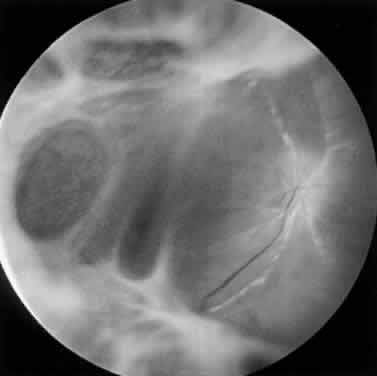

PORN syndrome is a progressive retinal infection with a distinct early, middle, and late stage (Table 2). The early stage is characterized by multifocal, homogeneous, opacified deep retinal lesions (Fig. 18). These lesions lack a granular border, which is a feature of CMV retinal infection. Lesions measure from 50 μm to several thousand microns in diameter and can be located peripheral to the arcades or in the macula at presentation. Early macular lesions are noted in up to 65% of patients, often appearing as central cherry-red spots67 (Fig. 19). Multifocal lesions rapidly progress to confluence and to full-thickness retinal involvement, forming large yellow-white areas of retinal necrosis with minimal retinal hemorrhage (Fig. 20). In eyes with initial peripheral involvement, progression often extends into the macula, and the entire retina may be involved within days. Primary retinal vascular inflammation does not appear to occur, although retinal vasculopathy in the form of sheathing and occlusion may be noted only within or adjacent to areas of retinal necrosis.67,68 A characteristic finding is perivenular lucency within areas of opaque retina, which may represent early clearing of necrotic retina71 (Fig. 21). Optic nerve abnormalities such as edema and hyperemia may occur and an afferent pupillary defect may be present secondary to severe asymmetric retinal necrosis or unilateral optic neuropathy. In end-stage PORN, dense white, plaque-like scarring with a “cracked-mud” appearance or retinal atrophy with peripheral hole formation may develop. Optic atrophy and narrowing of retinal vasculature typically are present.

Fluorescein angiographic features vary depending on the stage of PORN, but demonstrate involvement of the choroid, RPE, and multiple layers of the retina. In the early stages, peripheral retinal microvascular alterations are noted within and extending beyond deep retinal lesions.79 Retinal leakage is present in large areas of retinal whitening. With progression of PORN, pruning of the retinal vasculature—as well as capillary loss, RPE destruction, and choiroidal leakage—occurs. Disease reactivation at the border of normal retina is noted by a prominent brush-fire pattern of fluorescein leakage involving the retina, RPE, and choroid.